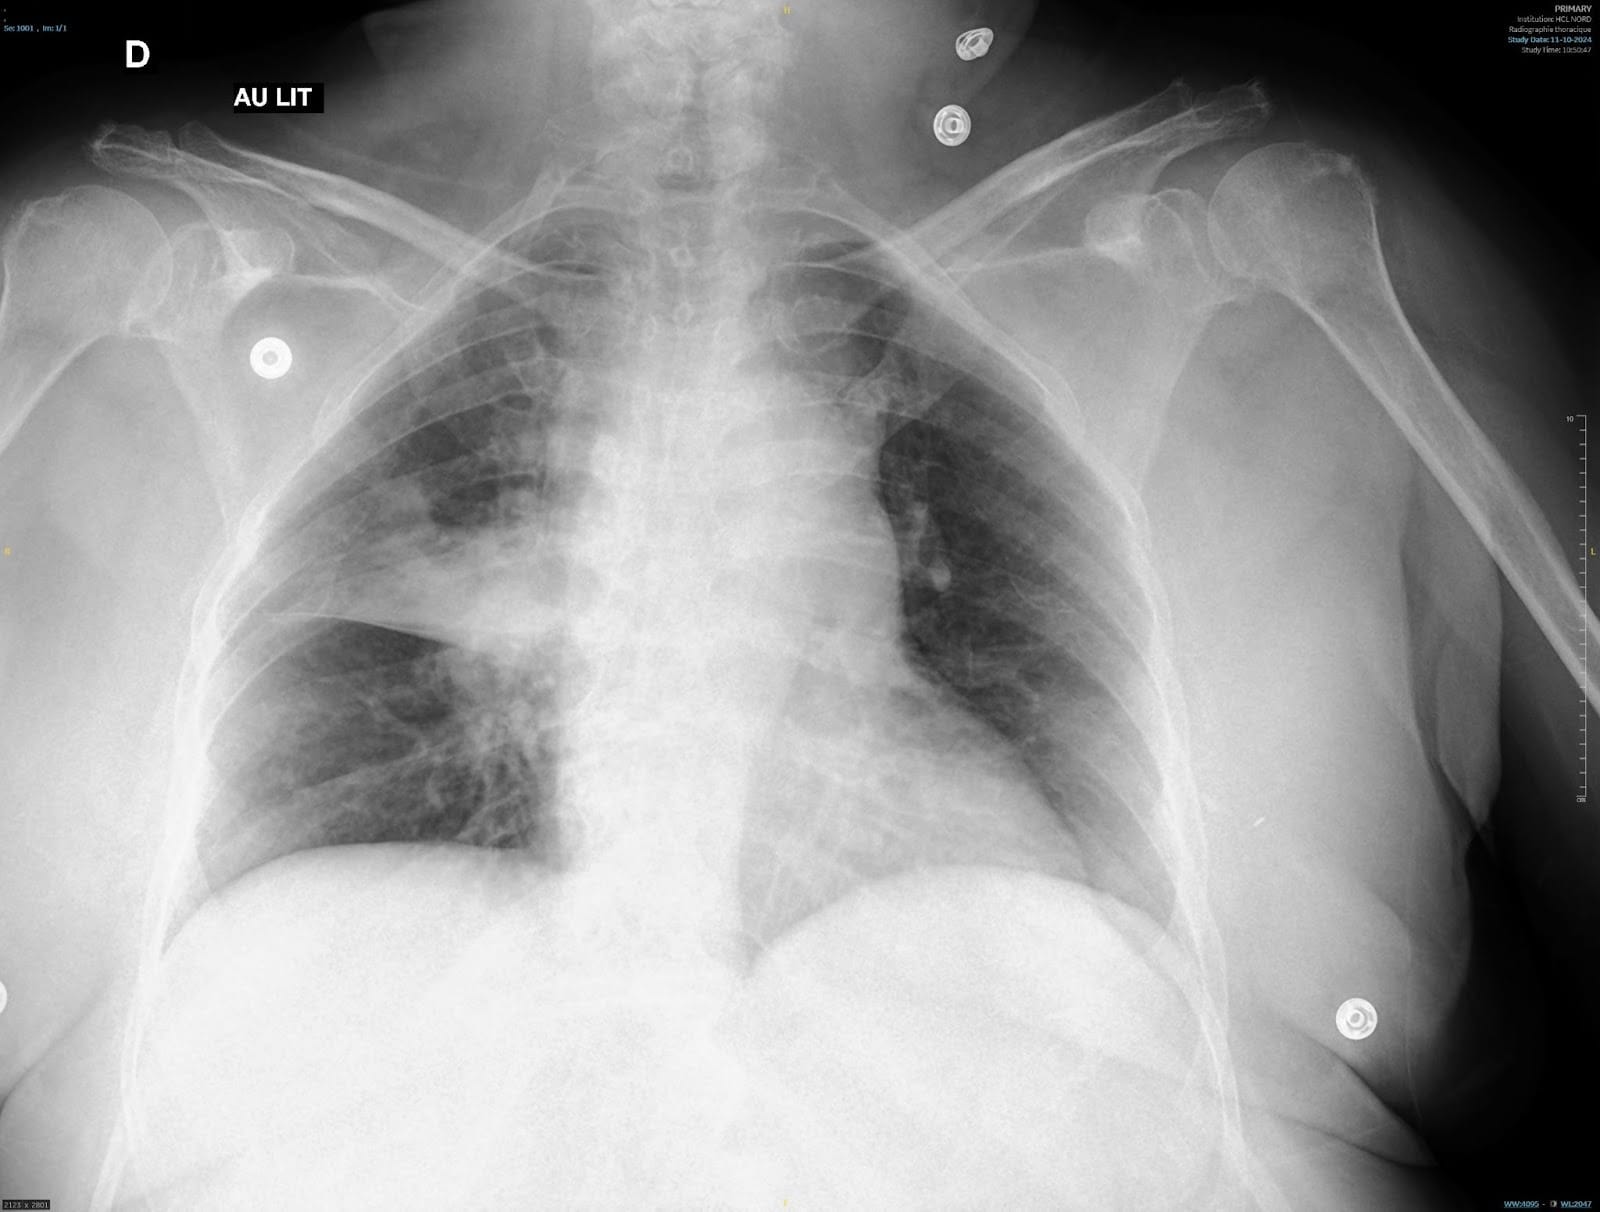

Interne aux urgences, vous recevez Mr Bajoul, 55 ans, pour dyspnée fébrile. Ce patient présente comme antécédent principal une BPCO Gold 2 sous bronchodilatateur de longue durée d’action, 1 inhalation le matin ainsi qu’une obésité avec IMC à 35. On note aussi une dyslipidémie non traitée, et un SAOS sous PPC.

Il vous dit avoir de la toux et de la fièvre depuis 48h avec des frissons, une dyspnée de moindre effort, une douleur latérothoracique droite.

Vous disposez de 8 minutes, temps de lecture compris pour :

- Exposer à l’évaluateur les éléments de votre examen clinique

- Dire à l’évaluateur les anomalies thoraciques probables au vu du contexte et de la radiographie